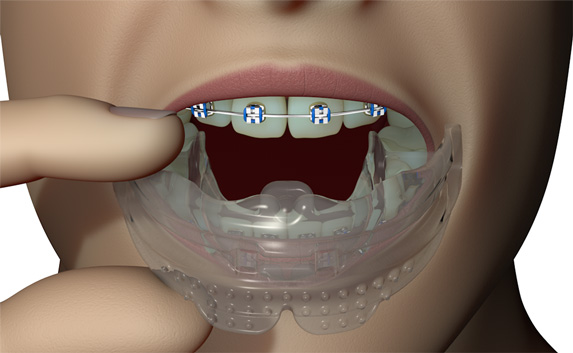

The B1 focuses on establishing nasal breathing and myofunctional habit correction for patients who are using braces. It is soft and flexible, giving the best compliance, while being adaptive to any arch form and malocclusion. It has small breathing holes to establish continuous nasal breathing and myofunctional features to promote correct habits. It also features braces channels to accommodate brackets and wires. The B1 is ideal for initial levelling and alignment with fixed orthodontics but can also be used throughout the entire orthodontic treatment plan.